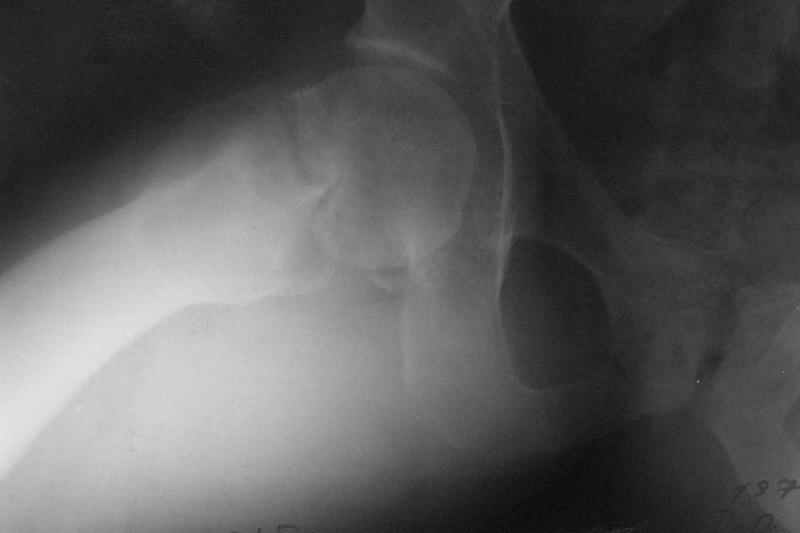

A male 31 years old treated elsewhere after not severe pelvic fracture 2 months ago, was managed non operatively. So the injury looked as a reason of his inability to elevate the leg. However at the recent x-rays the neck fractire was found. The patient already has been walking with partial weight-bearing.

Looking at the x-rays and the time since the injury, what is the optimal treatment for now? We discussed 1)leave as is, 2)2 cancellows screws as is, 3)valgus osteotomy. Total hip replacement looks unnecessary yet.